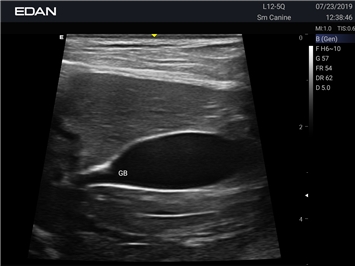

Ветеринарный ультразвук одним нажатием. Система Acclarix AX2 VET разработана с целью обеспечить бескомпромиссную производительность по доступной цене. Наличие уникальных двойных аккумуляторов в легком корпусе массой 4,5 кг из магниевого сплава позволяет системе Acclarix AX2 VET удовлетворять все потребности ветеринарных исследований, сохранив низкую стоимость.

EDAN Acclarix AX2 VET представляет собой специализированную ветеринарную ультразвуковую систему, сочетающую высокую производительность с доступной ценой. Благодаря продуманной конструкции и передовым технологиям, система обеспечивает качественную диагностику животных различных видов.

• Высокое разрешение для детальной диагностики

• Улучшенная визуализация глубоко расположенных органов

• Непрерывная автоматическая оптимизация изображения

• Адаптация к особенностям анатомии разных видов животных

• Повышенная точность исследований